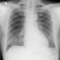

Dilakukan pemasangan DC jg dok, untuk memantau fluid balance pasien, dan jg pemeriksaan rontgen dan EKG dok.Terima kasih, dok.